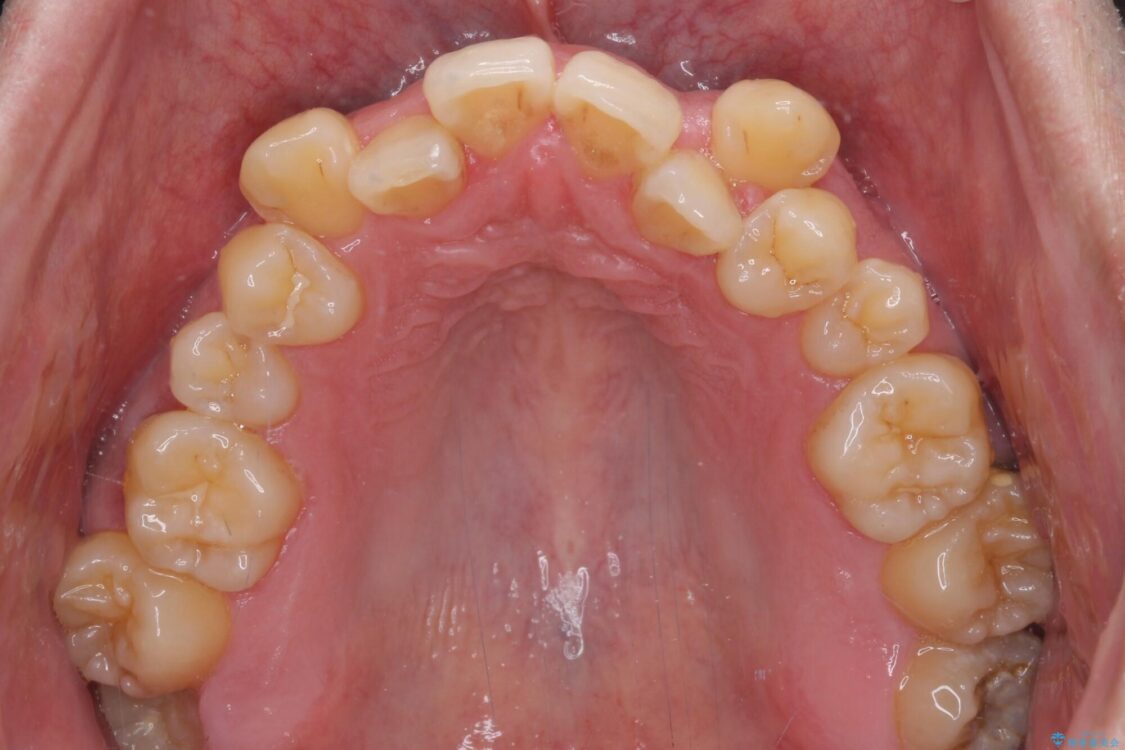

治療前

• 八重歯とクロスバイト 目立たないワイヤー装置で矯正治療 治療前画像